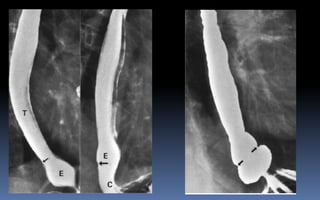

RADIOGRAFIA CONTRASTADA

“Económico y no invasivo”

Uso actual limitado por el avance de otras técnicas.

Indicación:

Patología funcional del tracto gastrointestinal:

esófago, estómago, duodeno, colon.

Alternativa de la endoscopia.

Estudios urológicos, ginecológicos y angiográficos.

Equipo utiliza monitores.